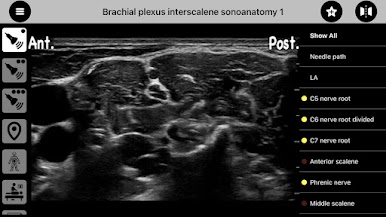

AnSo is a convenient resource designed to help anaesthetists identify common sonoanatomy, in a time efficient manner, within the busy operating theatre. It has been created by practicing anaesthetists with an interest in teaching ultrasound and regional anaesthesia.

AnSo helps identify not only the target structures but all the surrounding sonoanatomy. This more comprehensive understanding of the sonoanatomy helps detect anatomical variability, improves the safety and efficacy of procedures, and facilitates learning and teaching.

- over 250 ultrasound images with over 1500 sonoanatomy colour overlays,